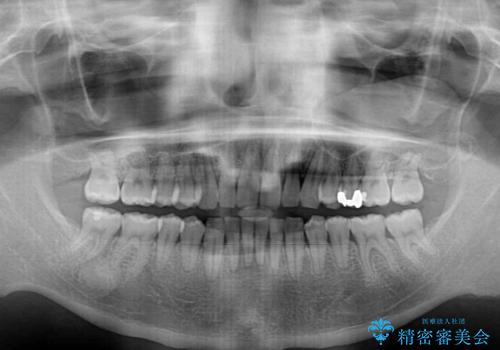

- 上顎前歯の突出感とすきっ歯を気にして来院された患者様です。

奥歯の咬み合わせを見ると、下顎に対して上顎が前方に位置していたため、補助装置により上顎歯列全体を後方に移動させ、その後インビザラインにて歯列全体を整えることとしました。

インビザライン開始前に奥歯の咬み合わせを変える補助装置は幾つかあります。

咬み合わせの強さや下顎の歯列の状態などによって、最適な補助装置を選択しています。

インビザライン単独で咬み合わせを改善することもできますが、治しきれない可能性が高いため、事前に補助装置で治しておくことは、治療の仕上がりの点で非常に重要となります。